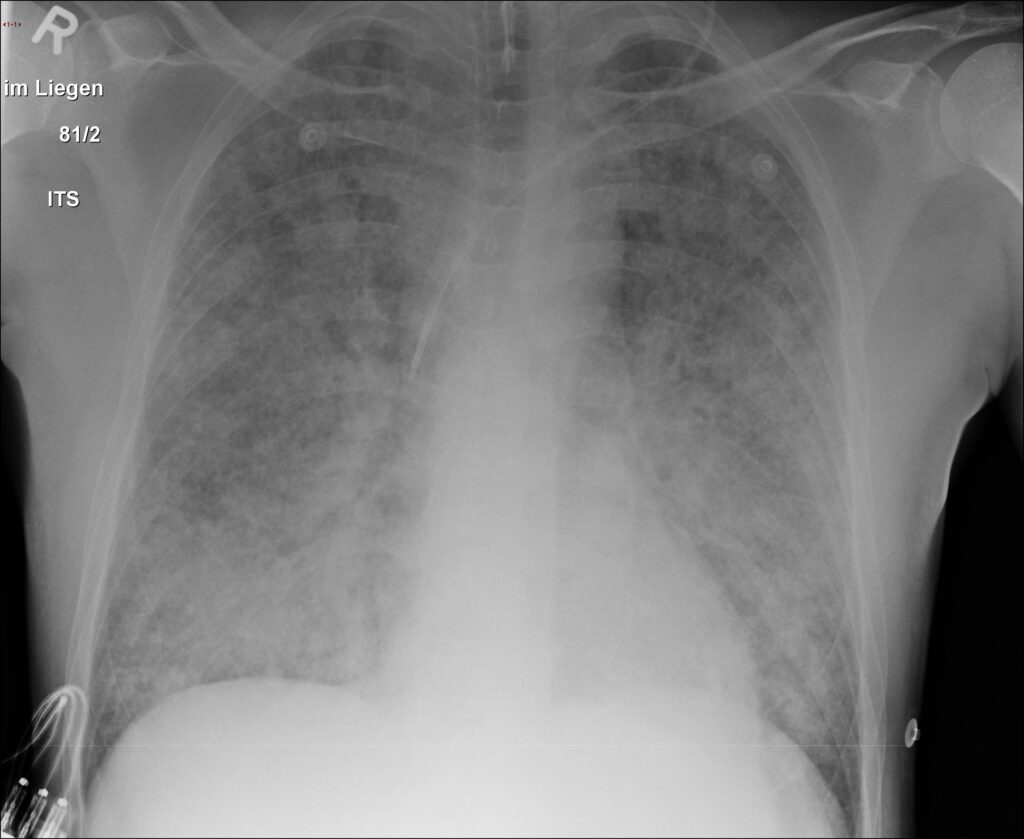

胸部 X 線または CT スキャンでは、肺の損傷や肺の出血を示す兆候が見られる場合があります。